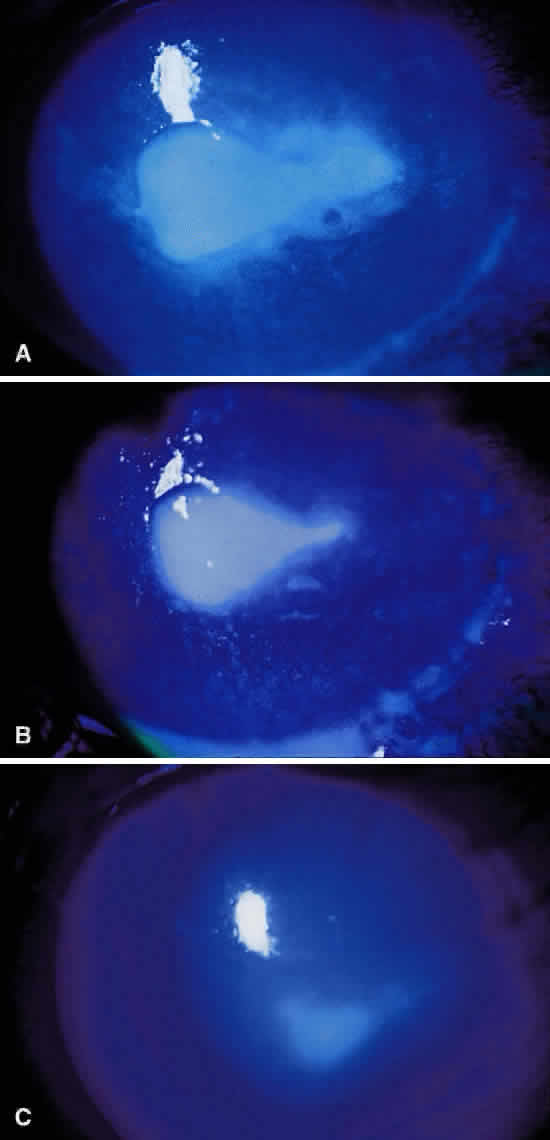

Infectious crystalline keratopathy is most commonly associated with S. viridans infection.43–45 This keratitis is characterized by discrete, white, crystalline, or fern-like stromal opacities, often under an intact epithelium, that are slowly progressive and have little associated corneal inflammation (Fig. 7). There is a strong association with prior topical corticosteroid therapy or penetrating keratoplasty. The condition has been termed infectious crystalline keratopathy and also has been reported with other organisms, including Haemophilus aphrophilus, Peptostreptococcus, and Staphylococcus epidermidis, as well as the fungal infections Alternaria and Candida tropicalis.46–49

|

A corneal biopsy may be necessary to gain access to the “crystalline” infiltrates for identification and culture of organisms. This may be accomplished using a disposable 2-mm dermatologic biopsy punch. These infections may be extremely resistant to therapy, requiring an extended course of antibiotics.